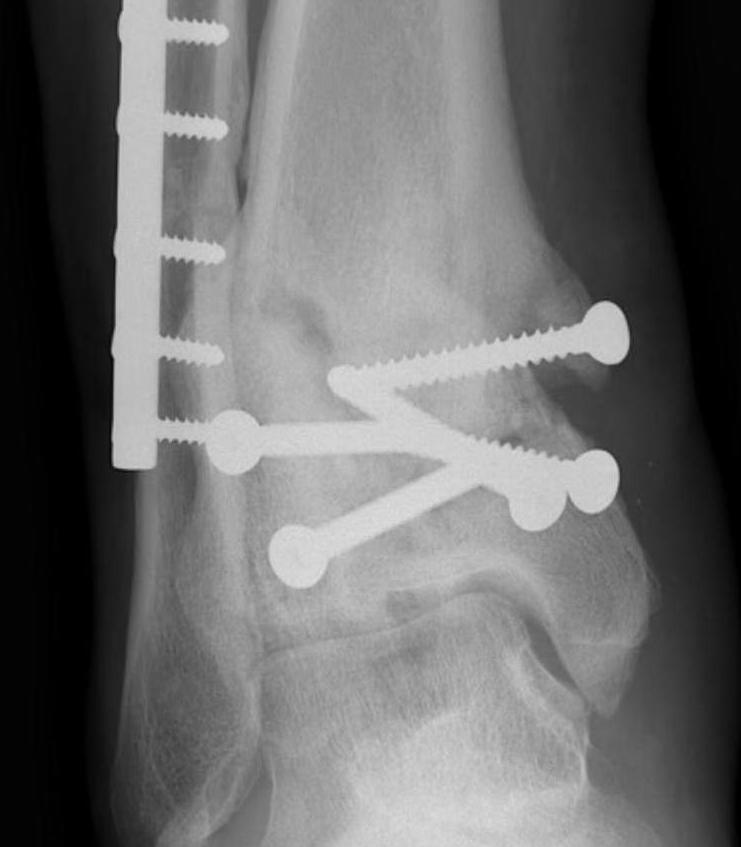

Xray

Ranges from anterior spurring to severe OA

80% of post-traumatic OA is varus

Supramalleolar Osteotomy

Varus OA treated with medial opening wedge supramalleolar osteotomy

Indications

Varus / valgus malalignment

Asymmetric OA with preserved cartilage in 50% of ankle (Grade 2 and 3A)

Technique